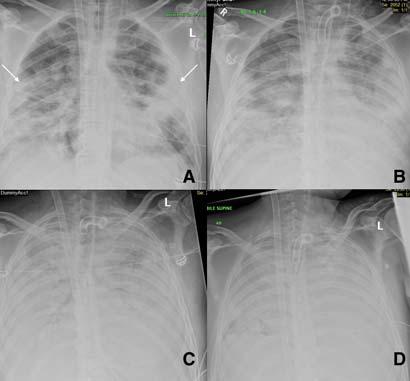

Atypical Findings :

Interstitial pattern of distribution has been reported apart from GGO and consolidation15. Pleural involvement is an atypical finding with pneumothorax and pleural effusions reported in some selective cases especially during disease progression/prolonged admission. Assisted ventilation related pathologies such as pneumomediastinum have also been reported18,19 (Fig 6). Nodular lesions have also been described and more easily recognized on CT13 (Fig 7).

Two of the very early reports from China and Hongkong had shown high sensitivity of CXR abnormalities in patients testing positive for COVID-1911,17. Wong et al12 , showed a sensitivity of 69% of CXR compared to 91% of RT-PCR with CXR abnormalities preceding positive RTPCR testing in 9% of patients. With these results, it was proposed to consider CXR as a screening tool especially due to limited availability and sensitivity of RT-PCR testing12. The same performance of the CXR, however, could not be replicated as the disease spread wider and more continents were involved. A recent study from New York City looked at 636 patients (confirmed and

Fig 6 — Serial CXR’s of a patient with COVID-19 showing development of atypical findings during the admission. The admission radiograph (A) demonstrates multifocal peripheral opacities (white arrow), followed by the development of right pneumothorax (black arrow) on day 7 (B) of admission with improvement in parenchymal changes subsequently on day 15 of admission (C). He developed extensive left pneumothorax (black arrow) and surgical emphysema (star)(D)of the chest wall later in the course. Images courtesy of Dr Amrita Bajaj, Glenfield Hospital, Leicester.

Fig 7 — Atypical presentation of COVID-19 in the form of nodules (arrows) seen on the CXR (A) and the corresponding CT (B). Image reproduced with permission from Covid-19 Database of the Fleischner Society.

symptomatic COVID-19) presenting to urgent care. They found a normal CXR in 58.3% patients and up to 89% of patients had normal to near normal CXR15. A similar finding was also seen in a study published from Korea15. The described CXR findings are not specific for COVID-19 and may also be seen in other viral pneumonias such as SARS and MERS. Many GGO and consolidative changes visible on CT may not be seen on CXR making it a less sensitive technique 11 .

CXR can be normal or near-normal in a large number of patients with COVID-19 and hence will not be a reliable test for diagnosis or screening.

Fig 8 — Serial CXR examinations in a patient showing disease progression. Presentation (A) film had bilateral peripheral hazy opacities that increased on day 7 (B) and became confluent. Further worsening of parenchymal changes on day 11 with the patient requiring extracorporeal membrane oxygenation (ECMO) support (C) with improvement in clinical condition and persistent parenchymal fibrotic infiltrates on day 23 of admission (D). Images courtesy of Dr Amrita Bajaj, Glenfield Hospital, Leicester.

CXR abnormality can precede RT-PCR positivity. Patients with abnormal CXR and high suspicion for COVID-19 should undergo repeat RT-PCR testing.

CXR in assessing severity of COVID-19:

Imaging can play a vital role in assessing the severity of COVID-19 patients. To assess the extent of disease involvement, a simplistic radiographic scoring system was used by Wong et al12. Each lung was graded from 0-4 based on the extent of involvement (0- no involvement, 1- up to 25%, 2- 25-50%, 3- 50-75% and 4 >75% involvement). The scores of each lung were added to get a final score. The severity score of CXR varied over the time and peak severity was seen at 10-12 days from symptom onset (Fig 8). As the disease progresses the GGO are replaced by areas of consolidation that either resolves or worsens to give ARDS picture11 (Fig 9). Various CT severity scores have shown good correlation with clinical severity of disease20 21. The degree of lung inflation at the initial CT can also predict adverse outcomes in patients with COVID-1922

CXR findings are at its worst at 10-12 days from symptom onset.

Simple CXR severity scoring can be used to assess the progression of disease.